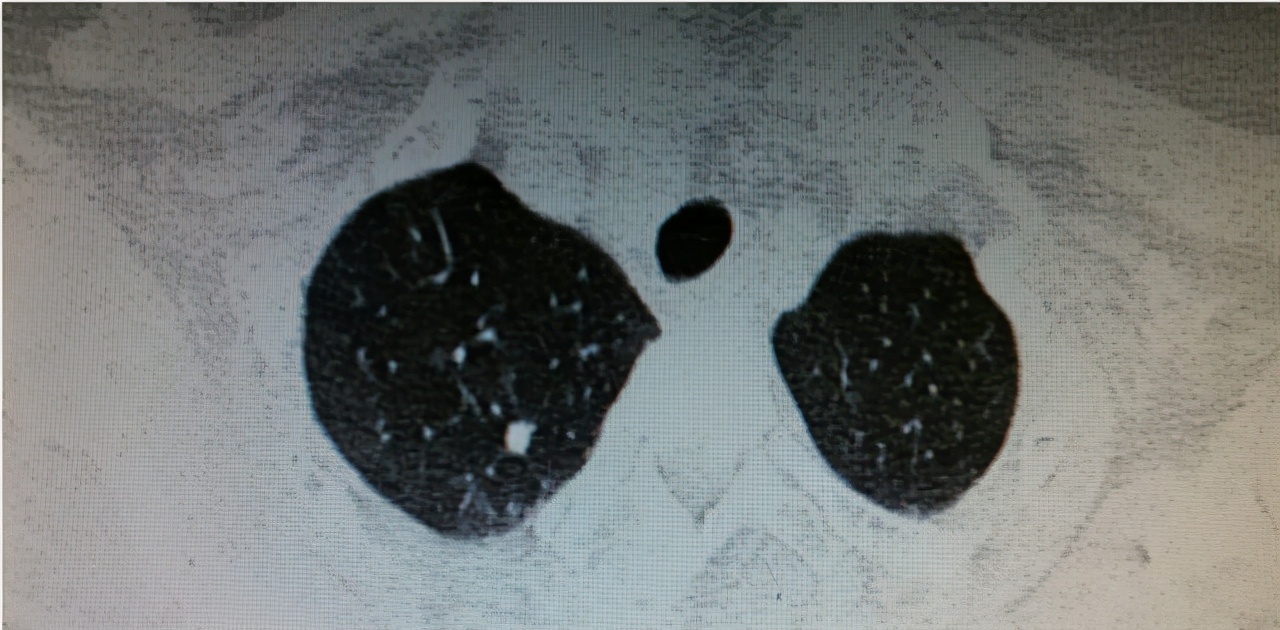

-影像检查

一般影像检查包含了 X线检查 及 心电图 检查项目,通过此类检查可查看胸廓是否扩张、肋间隙是否增宽及两肺野的透亮度的改变与否。